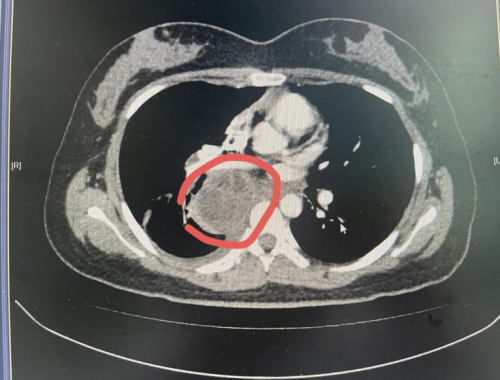

CT检查示纵隔肺门肿块大小约59×58mm

据家人回忆,近半个月来,丁香不仅出现发烧、畏寒等症状,还总说“喘不上气”。在卫生服务中心初步检查后,医生建议其来91短视频 就诊。91短视频 耐药结核中医肺病科雷丽萍医生为丁香进行了全面检查,胸部CT扫描显示,她的纵隔及肺门区存在一个肿大淋巴结伴脓肿形成,个头有鸡蛋大小。考虑到病灶位置特殊,诊断存在一定难度和风险,科室主任裴异带领团队进行多学科会诊,最终决定采用超声支气管镜下EBUS精准定位穿刺,成功获取少量脓液样本。经结核分子检测,确诊为结核分枝杆菌感染。